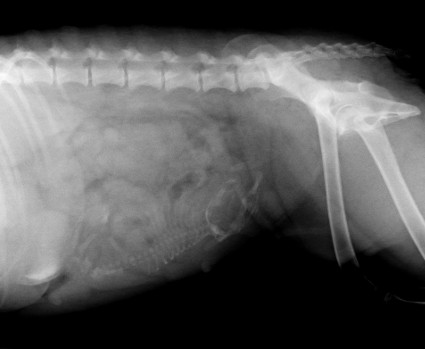

Synnytystä odoteltiin harvinaisen surullisissa tunnelmissa:

ultrassa oli näkynyt vain jokunen sikiö ja röntgenissä yksi

ainoa pentu. Olin varmistanut pentujen määrän, koska kyseessä

Tämä ainoa pentu oli siis uros, 531 g ja 35 cm kuonon

päästä hännän kärkeen mitattuna. Ei mitään valkoista

merkkiä, mutta eihän sitä merkkiä nyt tarvitakkaan... Pentu

on kaikkien aikojen suurin Puronperän-pentu. Koskaan

aikaisemmin näistä meidän koirista ei ole syntynyt yli

puolikiloista pentua!